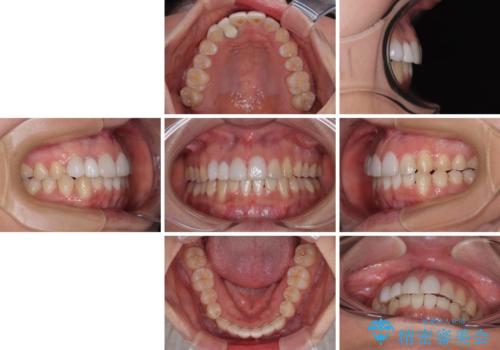

- 上下前歯のデコボコを気にして来院された患者様です。

インビザラインによる上下歯列の拡大と、IPR(歯と歯の間を削る)にるスペースの獲得により、前歯のデコボコを改善することとしました。

下顎前歯は後戻りを起こしやすいため、舌側を細いワイヤーで固定し、マウスピース型リテーナーで保定を行うこととしました。